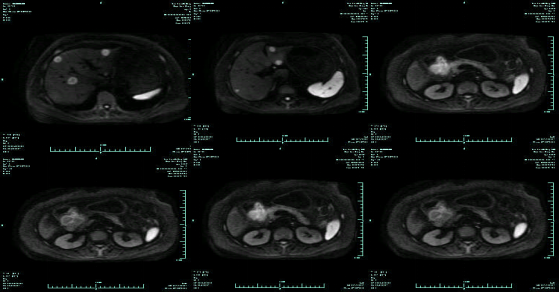

MR-H1

影像学检查结果评估:cPD。